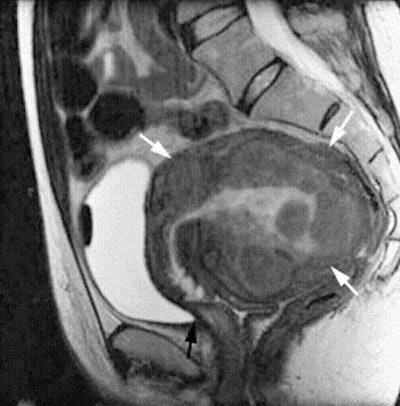

| This pre-UFE, sagittal FSE MR image depicts a large submucosal fibroid and several small intramural fibroids. Image courtesy of Dr. J. Mark Ryan. |